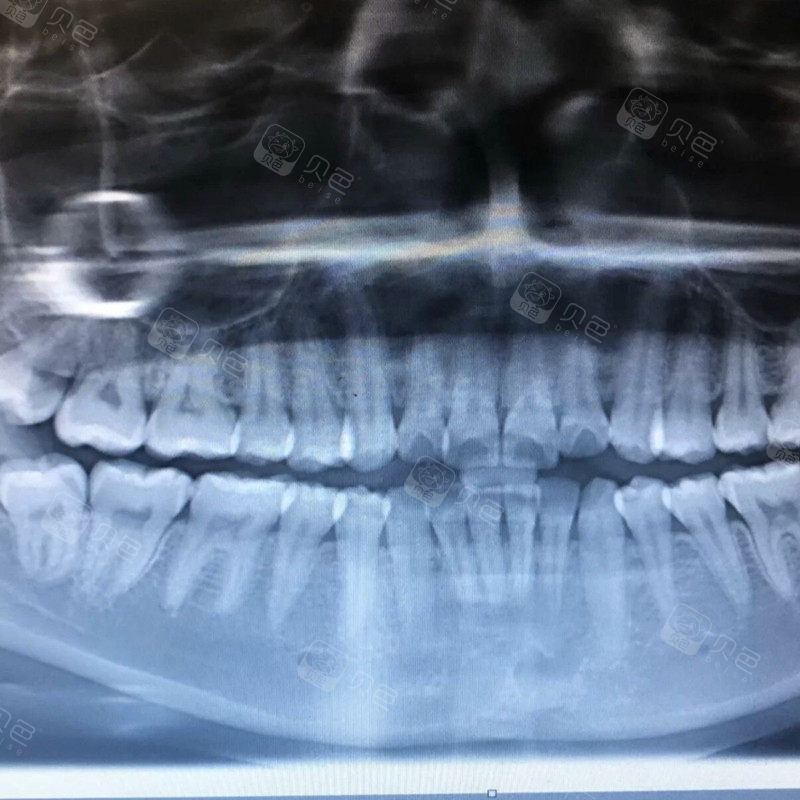

正常牙片,正常牙片图

正常牙片图

正常健康的牙片图片

健康牙片

健康的牙片图

全景牙片